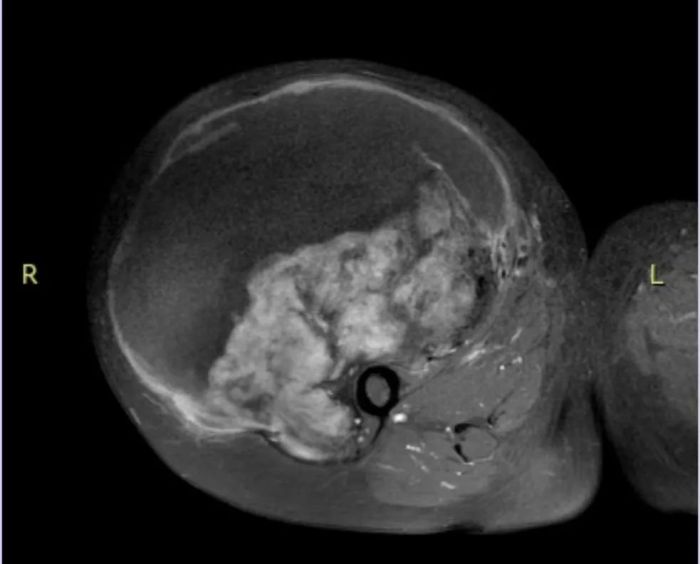

30年前,李阿姨发现右大腿内侧有一个约鸡蛋大小的肿块,行MRI检查后提示软组织肿瘤,因未出现红肿、疼痛等不适感,所以未进行手术。随着肿瘤逐渐长大,现已超过篮球大小,还伴有胀痛,使行走受限,严重影响了生活和工作,遂来到我院骨科就诊。

骨科积极为患者完善相关影像学检查,未见远处转移,排除禁忌后行穿刺活检,明确为纤维瘤病。幸运的是纤维瘤病为交界性软组织肿瘤,结合影像学表现,肿瘤未侵犯重要血管神经,有完整切除条件。如为恶性,则需行术前辅助放化疗,甚至截肢术。

经过前期充分的研讨和准备,由贵州医科大学附属肿瘤医院骨科学科带头人王东主任医师主刀,为该患者进行肿瘤切除术。术中清晰可见肿瘤与周围重要血管及神经关系密切,如稍有不慎,极有可能导致大出血或神经损伤。每一次操作,犹如刀尖上行走。经手术医护团队及麻醉医师团队的通力合作,历时5个多小时,肿瘤得以完整切除。切除的肿瘤重约5kg,超过篮球大小。术后大标本病理与穿刺标本病理一致,后续转入肿瘤内科进行观察治疗,经过医护人员的精心照料,患者现已康复出院。